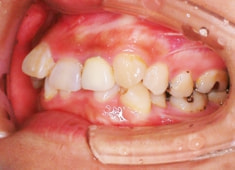

治療後(3年2ヶ月後)